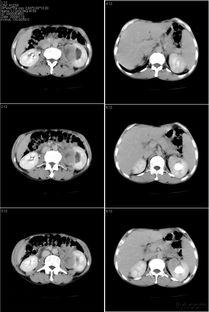

盆腔/腹部CT平扫+增强:是评估结肠癌及远处转移(尤其是肝、肺)的首选方法。能显示肿瘤的肠壁浸润厚度、周围脂肪间隙是否清晰、有无区域淋巴结肿大及远处器官转移。